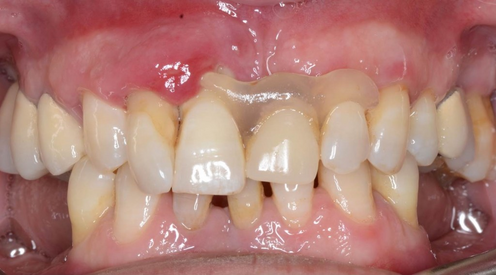

Second procedure after 4 months.

Intra-operative view of the second surgical session. All the vertical and horizontal defect was resolved.

Removing of the tenting screws.